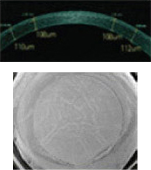

• 각막을 성형하여 원거리, 중간거리, 근거리를 안경 없이 선명하게 볼 수 있는 최신의 노안교정수술 방법입니다.

• 세계에서 가장 빠르고, 가장 미세한 레이저빔을 가진 아마리스 레이저를 이용하여 수술을 진행하며 1050Hz의 가장 빠른 안구 추적 속도로 안전한 수술과 신뢰있는 수술 결과를 제공합니다.